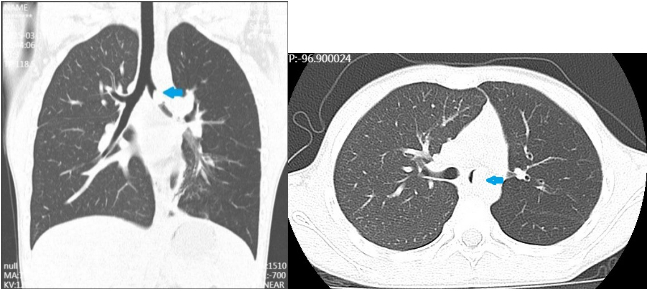

术前CT检查,箭头处为肿物

术前纤支镜检查,箭头处为肿物

入院后,李乐主任团队为小琪完善了胸部CT和纤支镜检查,发现肿瘤位于气管隆突附近,几乎将左主支气管完全堵住,如果肿瘤再侵犯气管隆突或者右主支气管,就会有窒息的危险。针对小琪的病情,胸外科迅速组织麻醉科、呼吸科、PICU、影像科等多学科会诊和讨论,决定尽快手术治疗,切除气管肿瘤并重建气管。